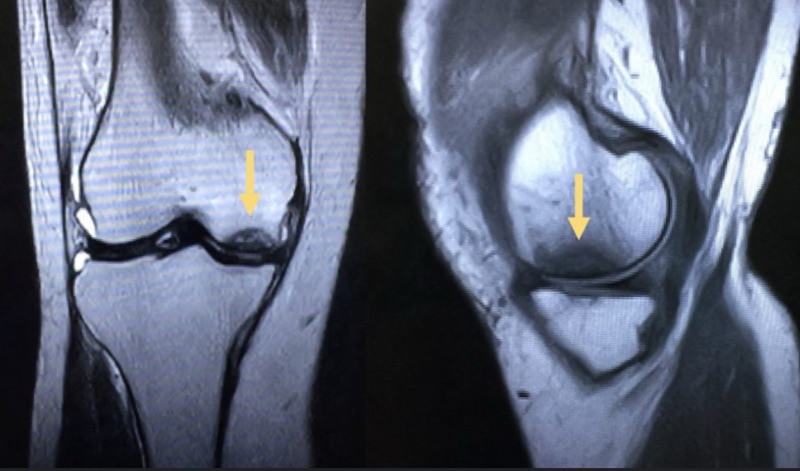

🔍 核磁共振是關鍵!

許多 AVN 病患在早期 X 光幾乎正常,但 MRI(核磁共振)能及早發現壞死區域、水腫與潛在骨塌陷,是診斷關鍵工具!